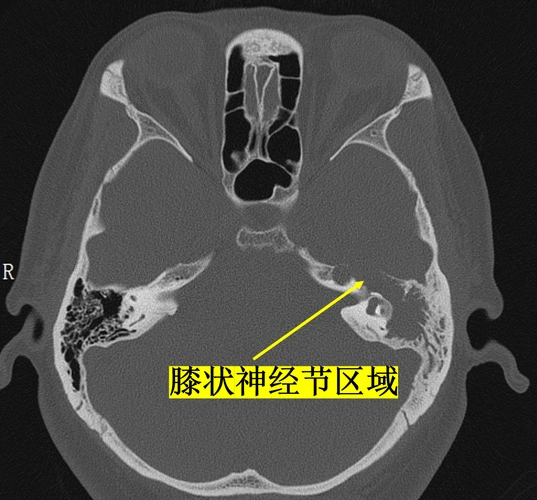

面神经瘤的影像学特点

该病典型的 mri 表现为双侧面神经发育不全,在平衡稳态梯度回波序列